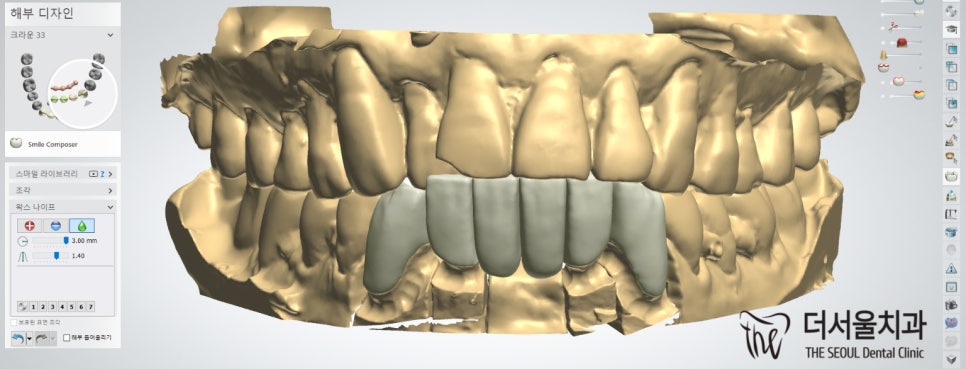

더서울에서는 전치부 브릿지 제작을 위해

컴퓨터 분석을 사용하여 디자인을 했습니다.

전치부는 심미성이 중요한 곳이기 때문에

티가 나지 않게끔 자연스레 만드는 것이 중요합니다.

『과연 어떻게 만들었을지 확인해 볼까요?』